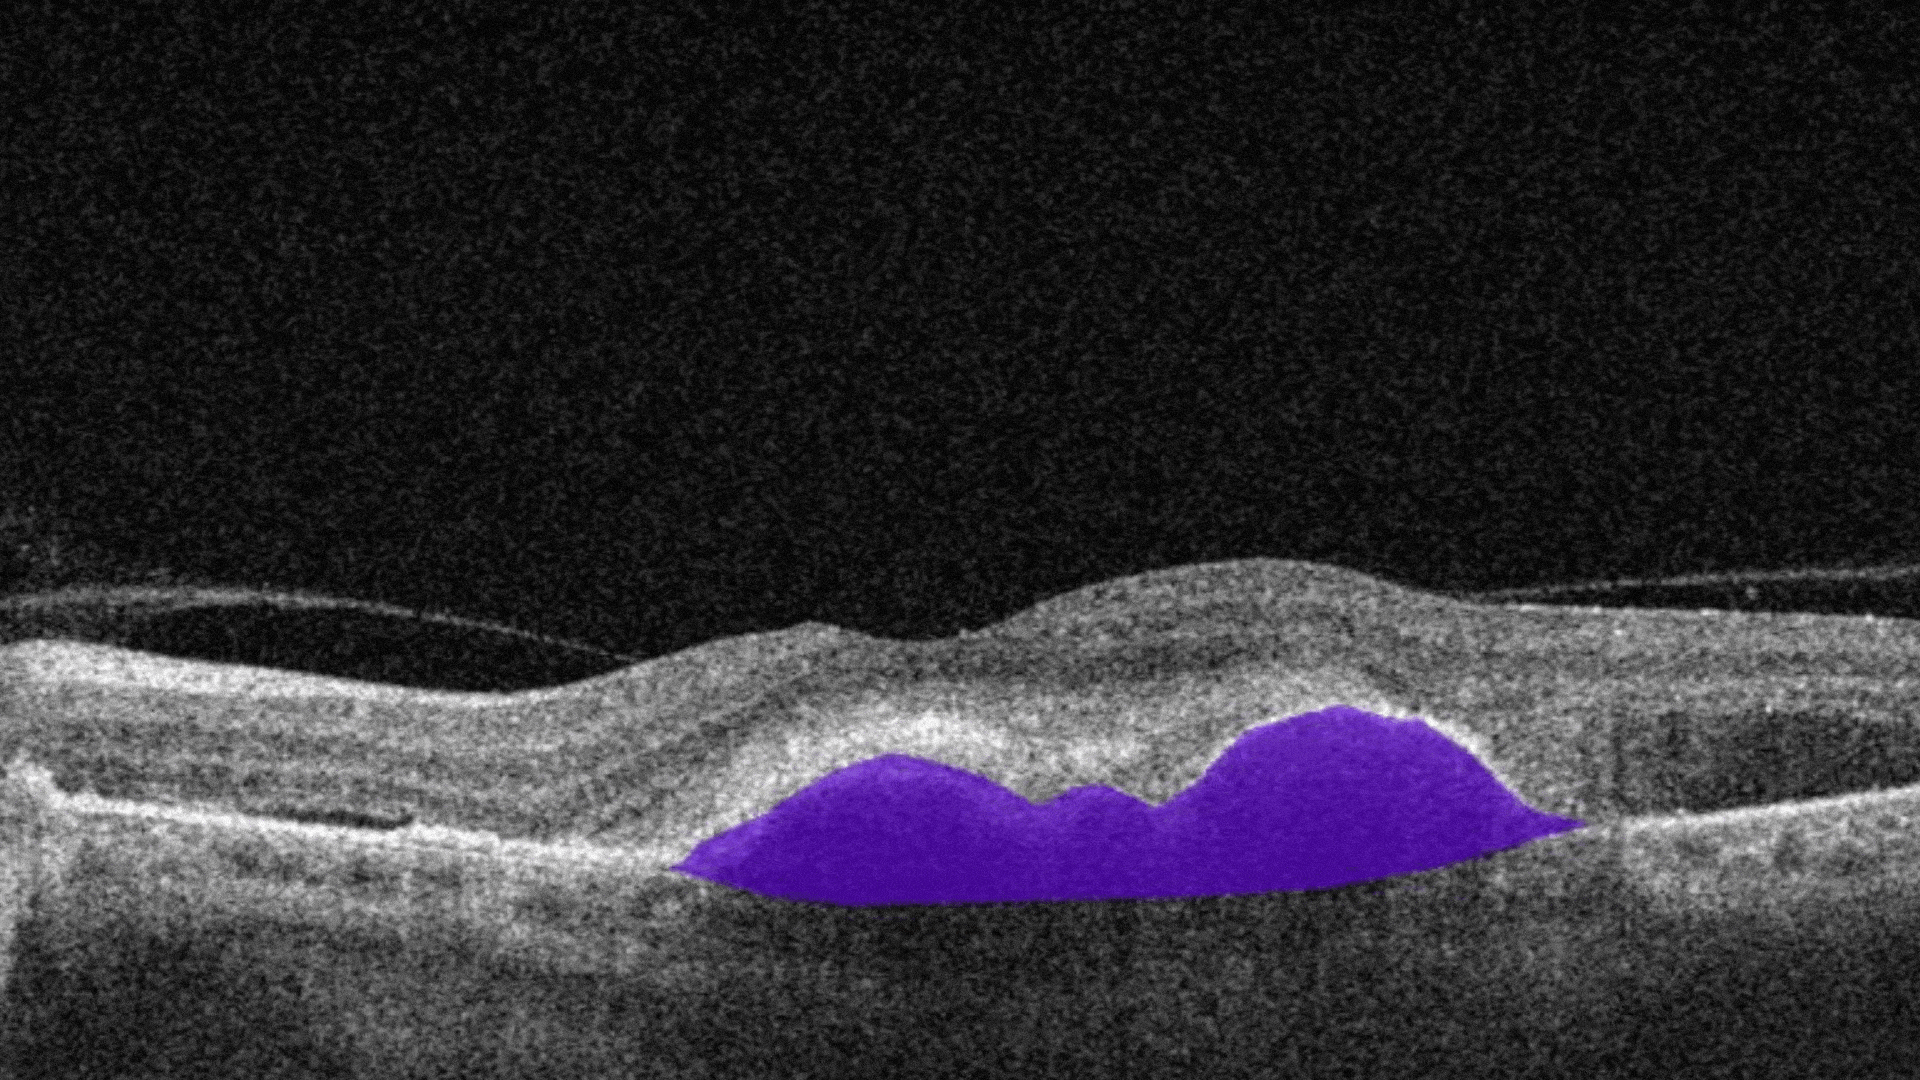

AI automates the selection of pathological OCT scans and the detection of 70+ pathologies and biomarkers.

More detailed screening means more early cases detected and more effective treatment as a result.